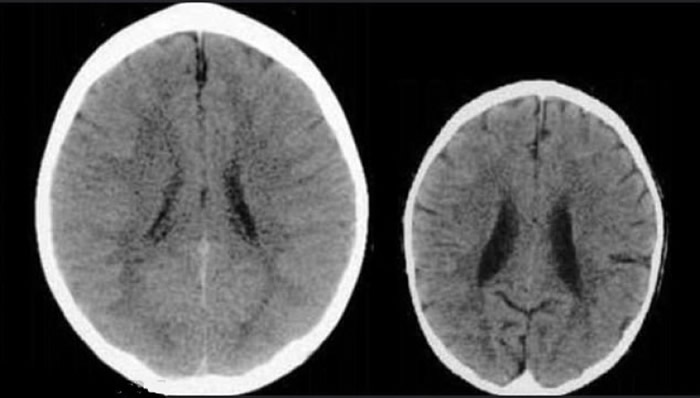

佩里长示的电脑扫描照片显示,缺乏关怀照顾的小童脑部(右)较其他小童小得多。

而美国德州儿童医院教授佩里(Bruce Perry)早前亦曾在一个医学研讨会上,展示2张健龄同为3岁的儿童脑扫描照片,其中一人在成长期间被疏忽照顾,其脑部体积明显较小,而且扫描出来的影像模糊,而该小童亦有严重心理创伤。佩里由此指出,缺乏关怀照顾,对小童脑部成长会造成极大影响。